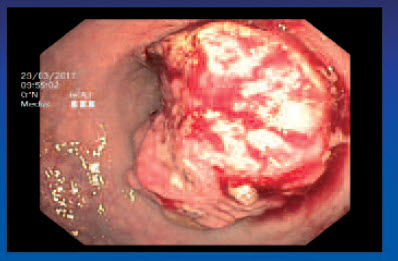

Tumor T2 N1 - kolonoskopie

Tumor T2 N0 - kolonoskopie